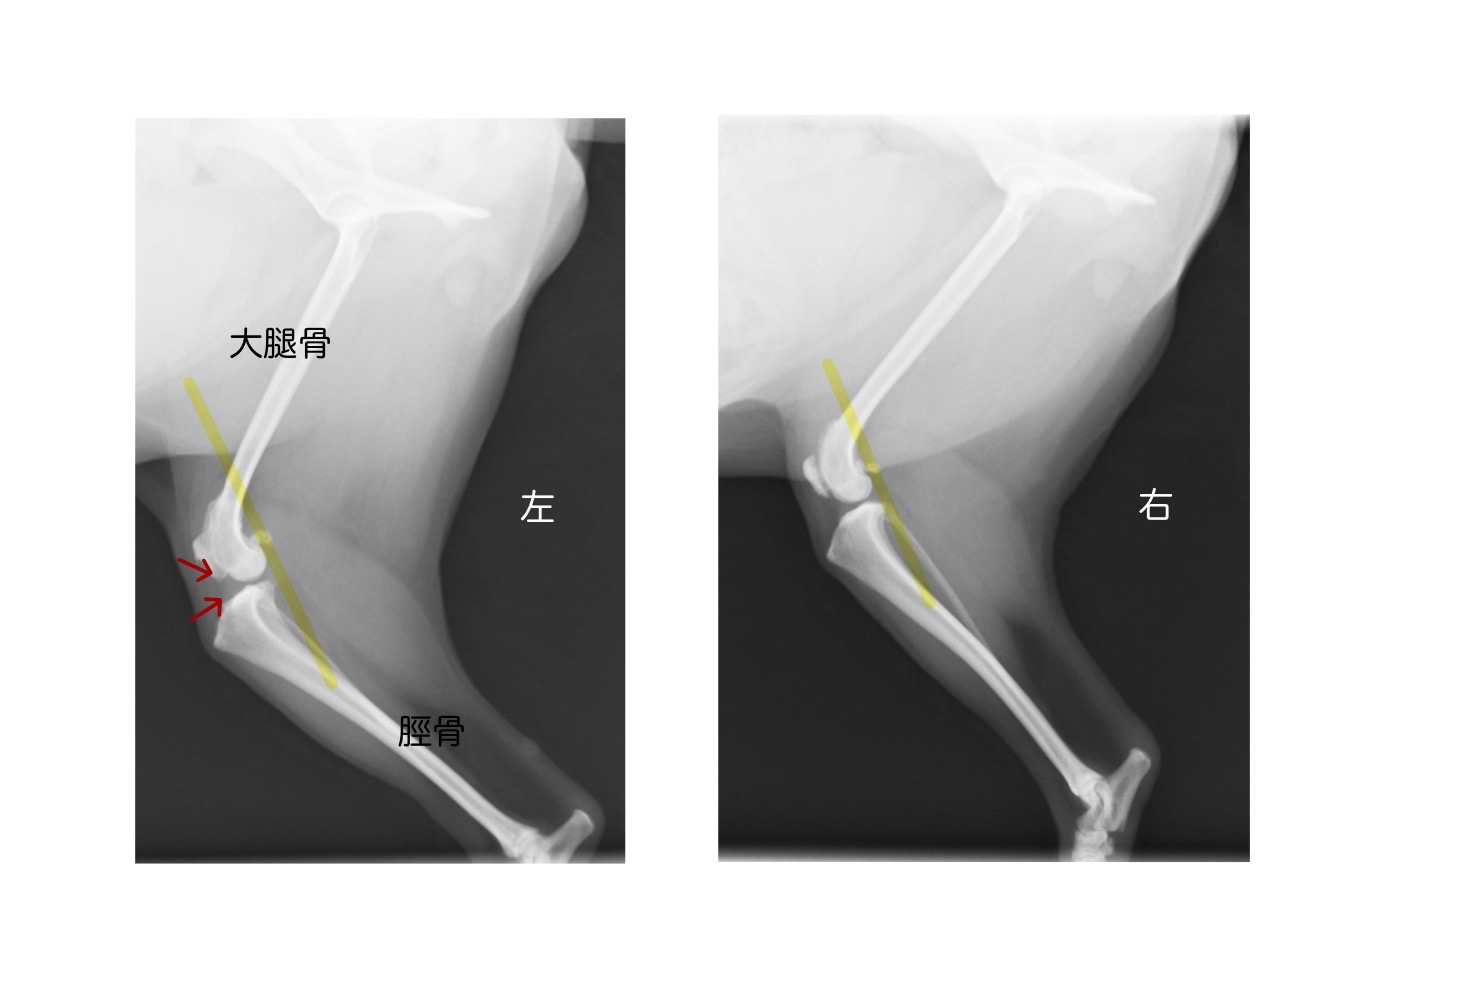

レントゲン検査の画像です。

右側が正常で左側が前十字靭帯が断裂してしまった脚です。

赤い矢印で示した部分がファットパットサインと呼ばれるもので、関節液が貯留することでうっすらと白い影が見られます。

また、膝関節が不安定になることから脛骨が大腿骨の前方へ変位します。マーカーのラインが正常ラインですが、左側は前方へ変位していることがわかります。